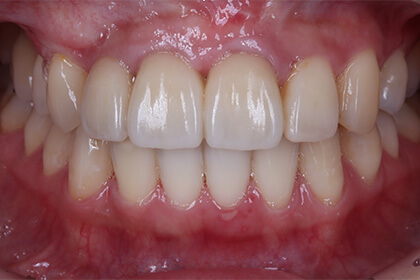

少数歯欠損

Before

After

基礎データ 20歳・女性 全身的既往歴および喫煙習慣なし

治療期間 2008年3月から2015年6月(約9年)

治療費 総額 254万円 【内訳】 歯周形成外科・インプラント埋入・クラウンブリッジ補綴 154万円 歯列矯正・顎の治療 100万円

主な治療 歯列矯正・抜歯・骨造成(GBR)・インプラント埋入・クラウンブリッジ補綴・歯肉形成

治療計画 正しい噛み合わせと、健康的かつ審美的な歯と歯肉を取り戻せるよう、治療計画を立案。

• 1.臼歯部で安定した噛み合わせができるための歯列矯正

• 2.失った上の中切歯(犬歯)をほかの歯で補い、アンテリアガイダンス(前歯誘導)を確立し、顎を動かす際に臼歯にかかる負担を軽減させる

• 3.前歯部分をインプラントとクラウンブリッジで補綴

• 4.歯周形成外科治療により、20代の女性が自信をもって生活を送れるよう口腔の審美性と機能を再建する